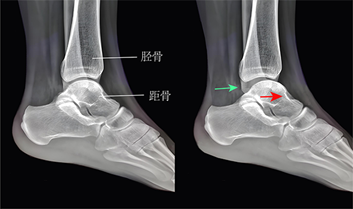

▶是踝关节外侧韧带复合体的重要组成部分(图1),其损伤后,踝关节的机械稳定性将受到严重影响。

▶经规范的保守治疗后,仍有10%至30%的患者最终会发展为慢性踝关节不稳(图2),严重的病例可导致踝关节炎。

图1:距腓前韧带(绿色)的解剖位置和损伤机制

图2:距腓前韧带损伤后,抽屉试验可见距骨前移(右图,红色箭头),踝关节间隙增宽(绿色箭头)